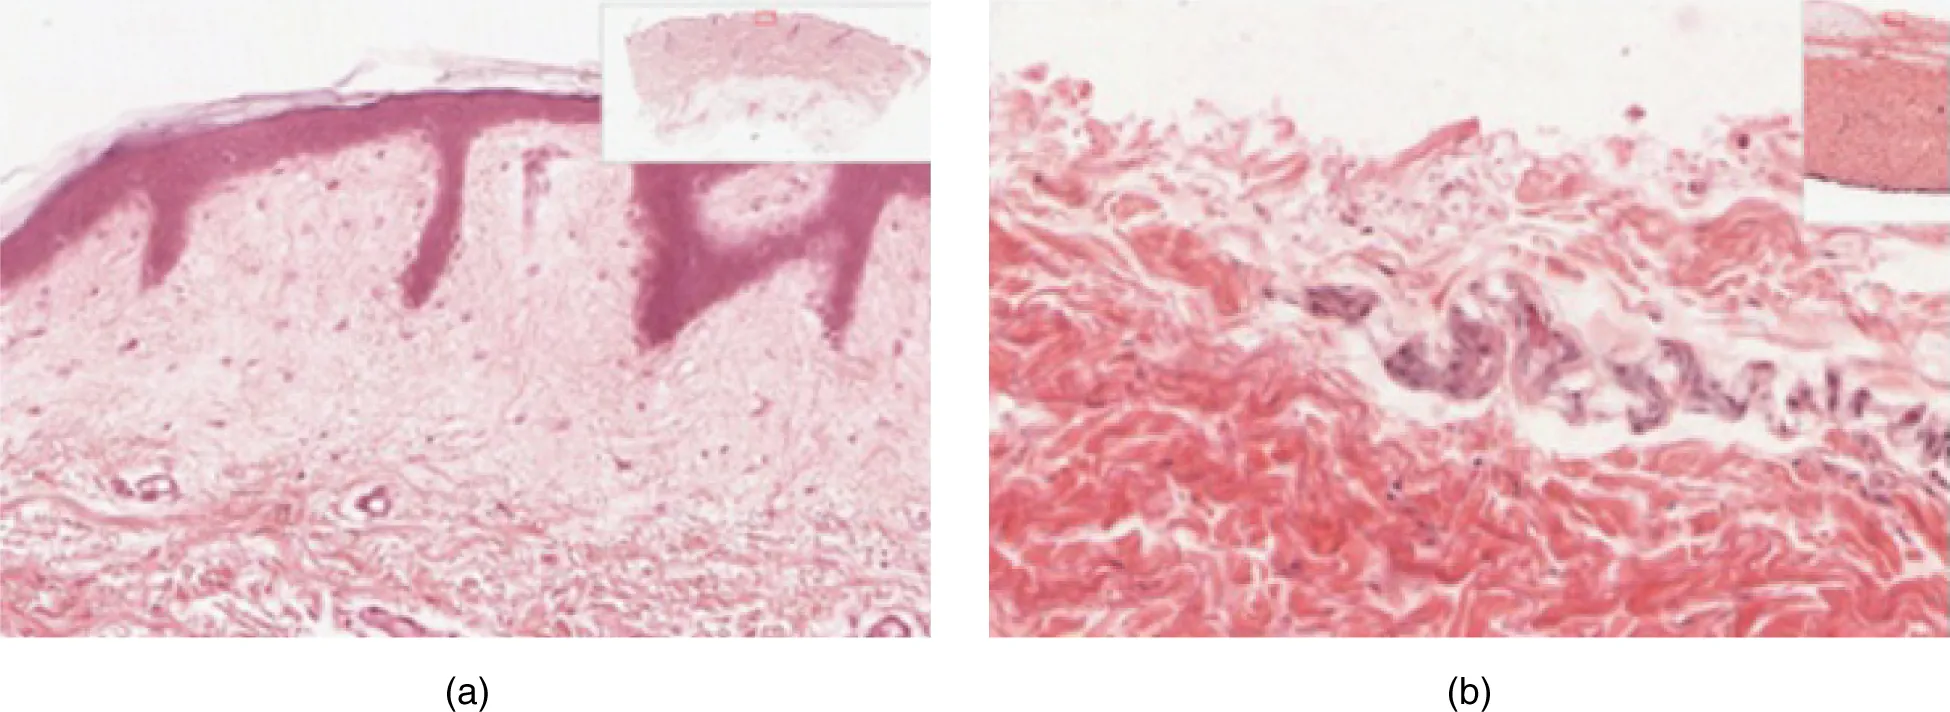

The Epidermis

The epidermis is composed of keratinized, stratified squamous epithelium. It is made of four or five layers of epithelial cells, depending on its location in the body. It does not have any blood vessels within it (i.e., it is avascular). Skin that has four layers of cells is referred to as “thin skin.” From deep to superficial, these layers are the stratum basale, stratum spinosum, stratum granulosum, and stratum corneum. Most of the skin can be classified as thin skin. “Thick skin” is found only on the palms of the hands and the soles of the feet. It has a fifth layer, called the stratum lucidum, located between the stratum corneum and the stratum granulosum (Figure 5.3).

Part A is a micrograph showing a cross section of thin skin. The topmost layer is a thin, translucent layer with irregular texture and areas where cells are sloughing off. The deepest layer is dark purple and extends into the third layer with finger like projections. The third light purple layer contains thin bands of fibers and small, dark cells. The fourth, and deepest layer, is darker than the third layer, but is still light purple. It contains thick fiber bands that are loosely packed. Part B is a magnified view of the epidermis of thick skin. It shows the topmost layer is five times thicker than the topmost layer of thin skin. The topmost layer of thick skin is also denser and less translucent than the topmost layer of thin skin.

Figure 5.3 Thin Skin versus Thick Skin These slides show cross-sections of the epidermis and dermis of (a) thin and (b) thick skin. Note the significant difference in the thickness of the epithelial layer of the thick skin. From top, LM × 40, LM × 40. (Micrographs provided by the Regents of University of Michigan Medical School © 2012)